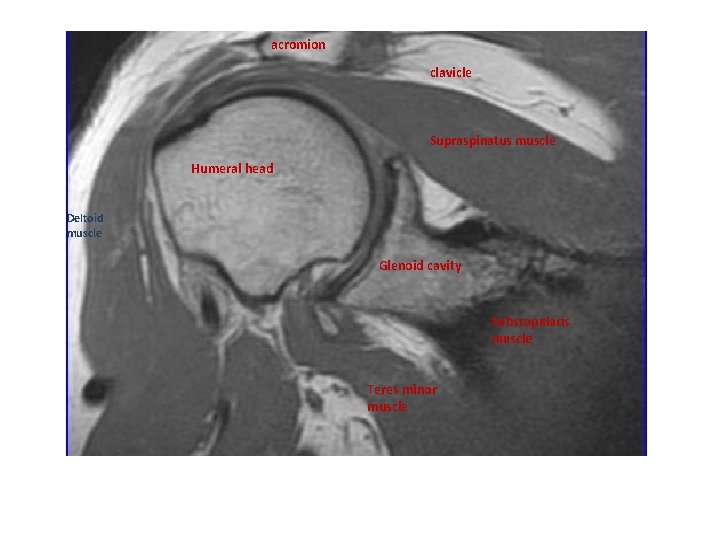

MRI

acromion clavicle Supraspinatus muscle Humeral head Deltoid muscle Glenoid cavity Subscapularis muscle Teres minor muscle